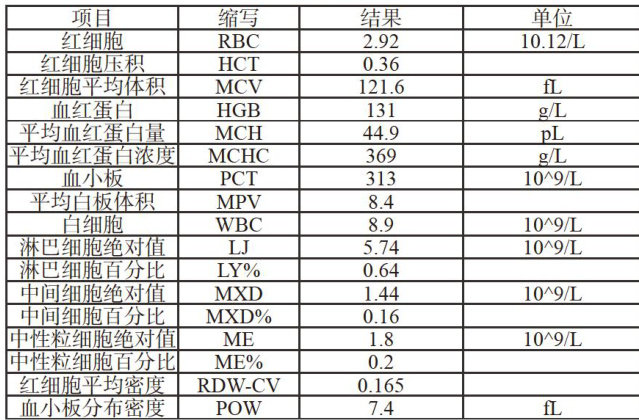

实践案例 | 浙江省某大型规模猪场蓝耳病引起流产的诊治案例分析

实践案例 | 浙江省某大型规模猪场蓝耳病引起流产的诊治案例分析